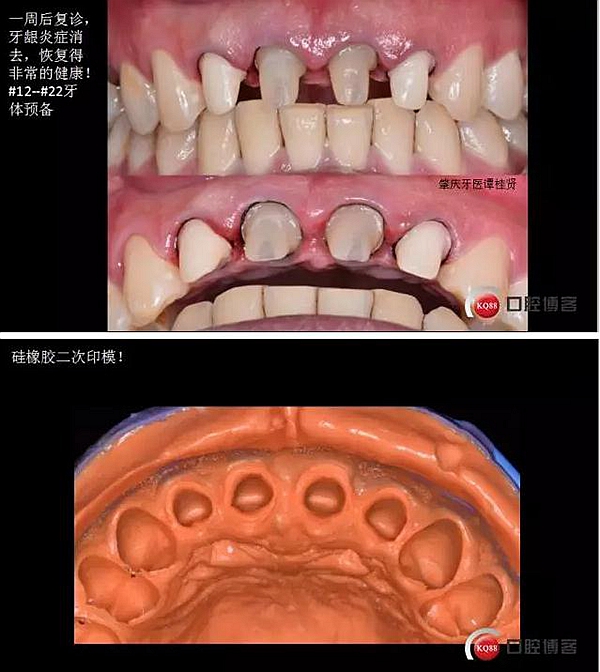

四診(一周后)

五診(又過了一周)

3.#12--#22氧化鋯全瓷冠修復